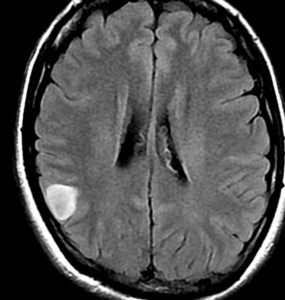

ぼーっと白くみえるのが星細胞腫です。この腫瘍はグレード2の腫瘍でした。実際にはこのMRIで白くにじんで映って見える領域より,腫瘍はさらに広い範囲に浸潤して広がっています。すごく大きいのですが,これでも無症状です。びまん性星細胞腫は脳の中にしみ込むように発育するので治療が難しいのです。手術でこれを全部とることはできません。浸潤性グリオーマ infiltrative gliomaの典型例です。

でも逆に,かなり限局性で正常脳との境界がはっきりしていて,手術で完全摘出できるびまん性星細胞腫もあります。上の例とは,病理診断が同じとは思えないくらいです。こういうのを限局性グリオーマ localized gliomaといいます。

両者ともにIDH1変異のある例でした。IDH変異型 びまん性星細胞腫 グレード2といってもかなり臨床像と治療法,予後に異なりがあります。